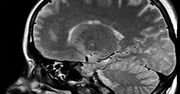

Niektóre dzieci, które przeszły koronawirusa, zmagają się z nową, groźną chorobą - z tzw. zespołem pocovidowym. Z silnymi objawami tej infekcji tylko w samym Szpitalu Dziecięcym w Krakowie na intensywnej terapii leży już kilkanaścioro małych pacjentów - donosi "Gazeta Wyborcza". Lekarze twierdzą, że zespół pocovidowy może być nawet groźniejszy od koronawirusa.